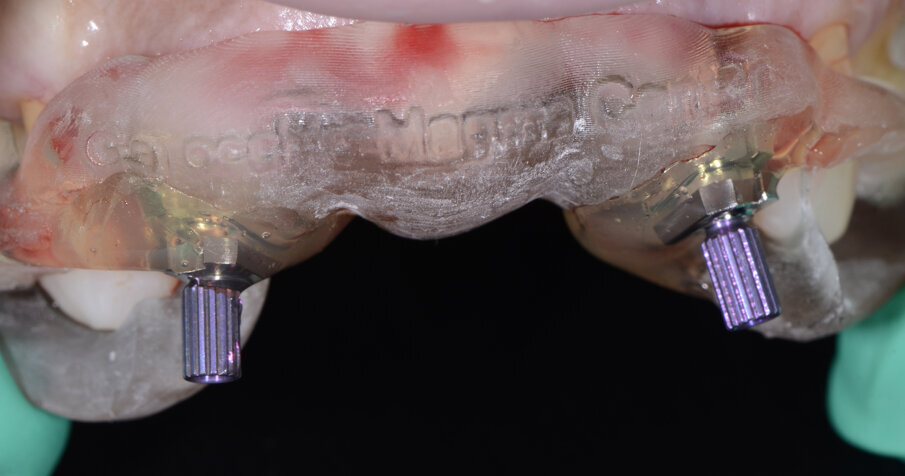

Alloggiamo la dima protesica (Fig. 33), e blocchiamo i transfert con della resina trasparente (tecnica DIL) (Figg. 34, 35). In questo modo possiamo far riposare il paziente in studio dopo appena 35 minuti dall’inizio dell’intervento. La dima protesica, infatti (Fig. 36) con i transfert inseriti viene completata con l’unione degli analoghi ai transfert (Fig. 37). L’insieme così composto viene riadattato sul modello master digitale iniziale (Figg. 38-40) sul quale era stata costruita sia la dima chirurgica che la dima protesica come anche il provvisorio. Gli analoghi vengono bloccati sul modello con resina trasparente (Figg. 41-43). Alloggiamo il provvisorio sul modello master digitale così ottenuto (Figg. 44, 45).

Fig. 34 - Transfert bloccati con resina trasparente.

Fig. 35 - Rimozione dima protesica.

Fig. 36 - Dima protesica e transfert bloccati.

Fig. 37 - Dima protesica e transfert bloccati.